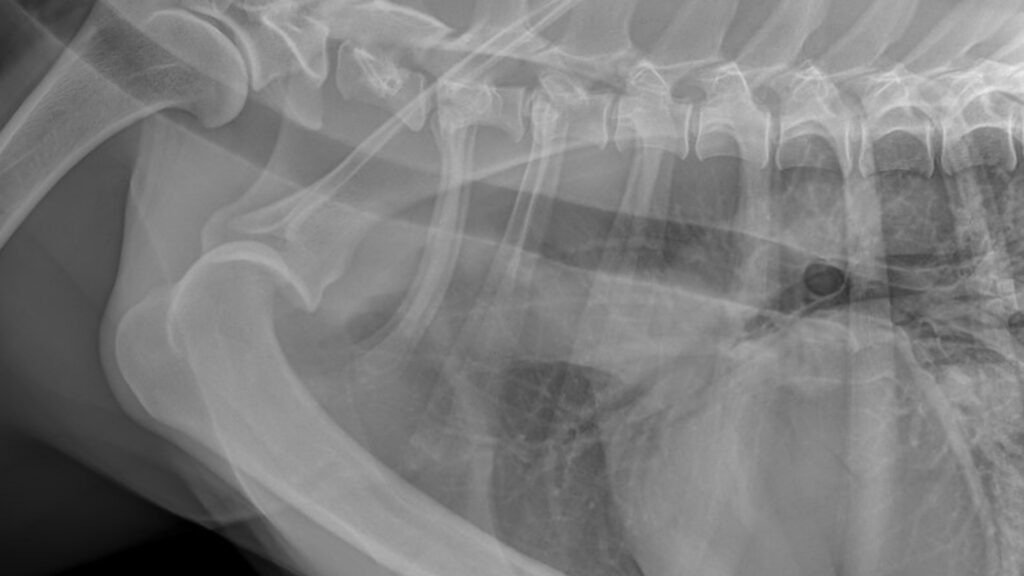

Hind limb

Conditions affecting the hind limb, including the hip, hock, and knee joints.